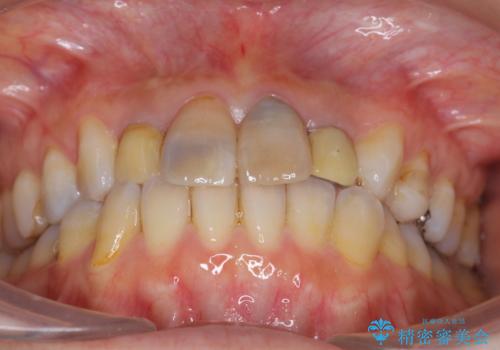

- 「黒ずんで、見栄えの悪い前歯をきれいにしたい。」と、前歯のセラミック治療を希望され来院されました。

全て根管治療のすでになされている歯の変色で、オールセラミッククラウンによる審美性の改善を計画します。